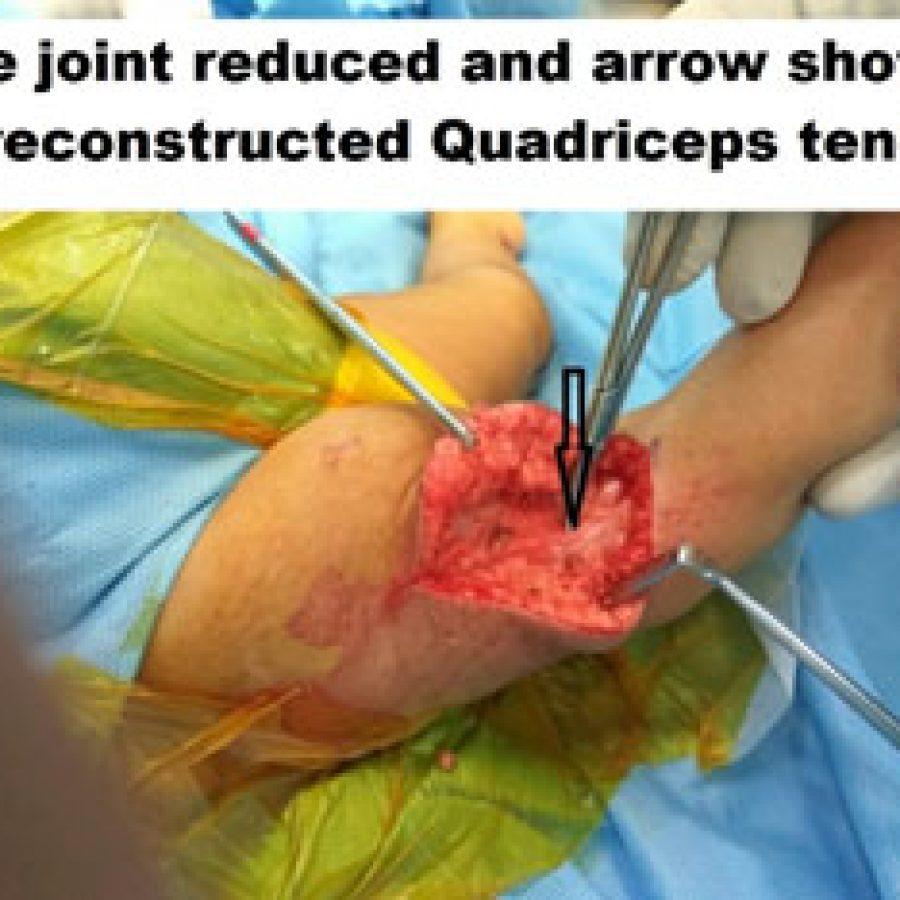

GENU RECURVATUM (CONGENITAL DISLOCATION OF THE KNEE)

Recurvatum is a spectrum disorder where it could be due to mal-positioning in utero or could be part of a genetic spectrum.

Pathology-

There is tightness in the quadriceps tendon, with anterior subluxation of the hamstring tendons. The collateral ligaments are tight as well.

The deformity is visually apparent and is noticed at birth. Treatment usually consists of serial plaster casting and once knee joint reduced, Pavlik Harness for treatment of the associated DDH

Late Presentation

If a child presents late, then the child has to be treated operatively by soft tissue release and open reduction of the knee joint.